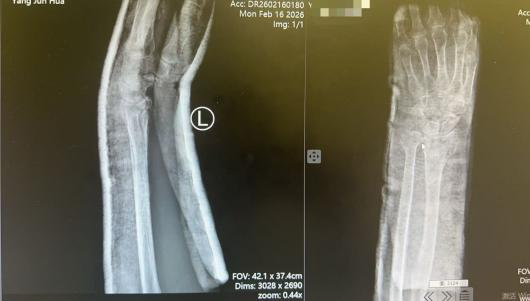

接诊医师薛安邦第一时间为杨奶奶开展详细查体,结合X线影像学检查,明确诊断其为左尺骨远端合并桡骨远端粉碎性骨折,骨折端移位明显,伤情复杂棘手。考虑到患者年事已高,手术治疗不仅面临麻醉风险,术后恢复周期长、并发症发生率也会显著增高,杨奶奶及家属在知晓手术相关风险后,明确提出拒绝手术、希望采取保守治疗的诉求。

复位完成后,复查X线片显示,患者骨折端对位对线良好,完全达到临床治疗预期,杨奶奶的腕部疼痛也得到明显缓解,整个诊疗过程顺利高效。“本以为老人年纪大了,骨折这么严重肯定要开刀,没想到薛医生几下手法复位就解决了问题,老人少受了大罪,太感谢红会医院的医生了!”杨奶奶的家属对治疗效果赞不绝口,连连向手法复位室团队表达谢意。